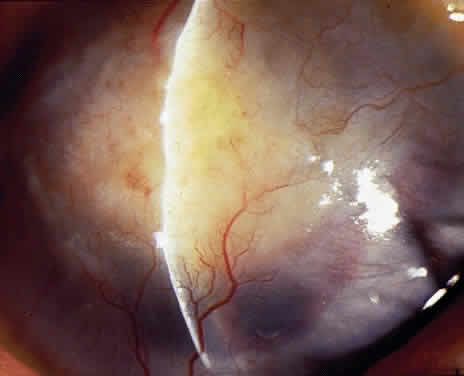

OCULAR FINDINGS. One of the few truly diagnostic and pathognomonic physical signs in clinical medicine is a Kayser-Fleischer corneal pigment ring found in patients with Wilson's disease (Fig. 5).This ring is recognized as a golden-brown, ruby-red, or green band of 1.0 to 3.0 mm, starting at the limbus but at the level of Descemet's membrane.53 The color of the ring is presumably caused by scattering and reflection of incident light and by photointerference effects created by the layers of copper granules. Such variables as size, shape, and unit density of the granules may account for the different appearances of the Kayser-Fleischer ring. The course of the Kayser-Fleischer ring has been well documented.54,55 The site of earliest pigment deposition is an arc in the superior periphery of the cornea from the 10- to 2-o'clock meridian. The arc spreads slowly toward the horizontal plane and gradually broadens. Later in the progression of the ring formation, a band appears inferiorly as a crescent stretching from the 5- to 7-o'clock positions. In time, the two arcs meet. With treatment, the sequence of events is reversed, and after the copper has reabsorbed, a pitted or beaten silver pattern may become apparent at the previous site of the ring. This is an indication that treatment has produced a negative copper balance.49 Decreased visual acuity is not a problem. Rarely, copper is deposited in the crystalline lens, giving an anterior subcapsular “sunflower” cataract.

PATHOLOGY. Electron microscopic, x-ray energy spectroscopic, and atomic absorption spectroscopic studies of the Kayser-Fleischer rings have revealed electron-dense granules rich in copper and sulfur in both the peripheral and the central region of the cornea, but more abundantly at the periphery. The association of copper with sulfur suggests that a sulfur-containing moiety functions in binding copper.59